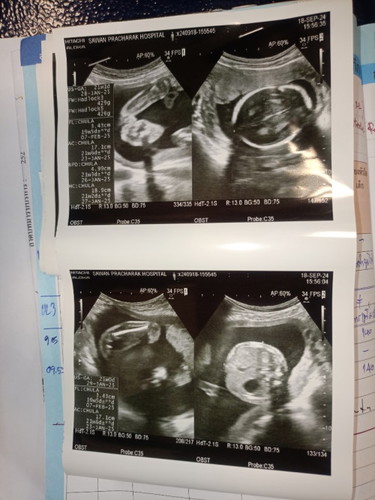

แม่ๆช่วยดูหน่อย ผู้หญิงหรือผู้ชายค่ะ

หมอบอกว่าอาจจะผู้หญิง แม่สั่งของผู้หญิงมาเยอะแล้ว แอบกลัวเพี้ยนตอนใกล้คลอดจัง

ผู้หญิงล่ะค่ะคุณแม่ ดีใจด้วยนะ บ้านนี้ชายจ้า